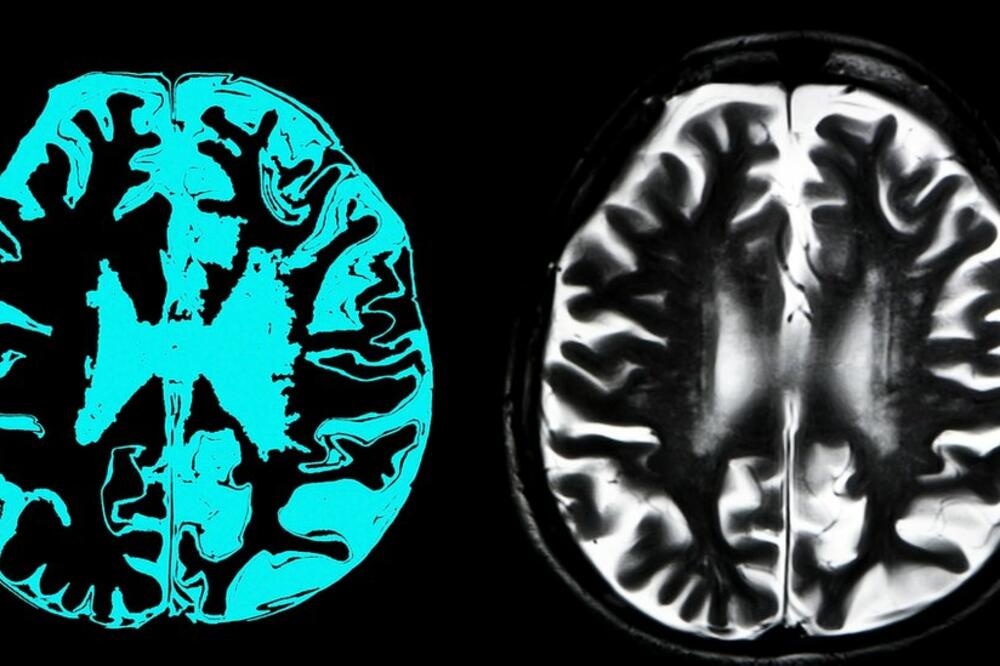

Ilustracija, Foto: Getty Images